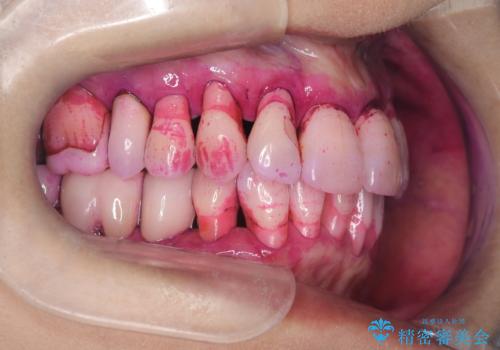

- 歯周病で歯茎が下がり根っこの部分が見えている状態で3か月のメンテナンスをコンスタントに通われている方です。

ブラッシングは歯間ブラシや部分歯ブラシなどの補助道具も使用し時間をかけて丁寧に磨いていらっしゃるのですが、ブラッシング圧に気を付けながらの為バイオフィルムが根っこの部分に残っているのです。

いつも時間をかけて丁寧に磨いていらっしゃるようですが染め出しをしてみると歯茎が下がっている部位はバイオフィルムの付着が見られました。